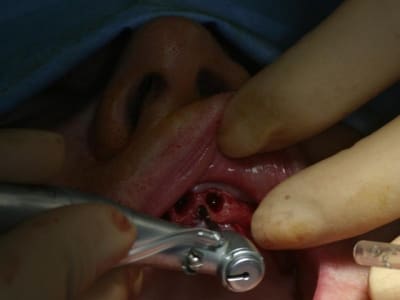

bon, toujours aussi speed je suis, mais après certaines réclamations, et malgrès ma réticence à poser un cas non "consolidé", voici en avant première mon premier all on 4, version photos ratées et non retouchées, mais... speed je suis je vous disais ;)

sto le bla bla, et pasons le diaporama... bon voyage au pays de la mise en charge immédiate totale au maxillaire de fille carole sur dame ginette, une patiente en or que j' adore, et pour qui je suis très très heureuse d' avoir pu réaliser cette chirurgie et la première étape prothétique.....